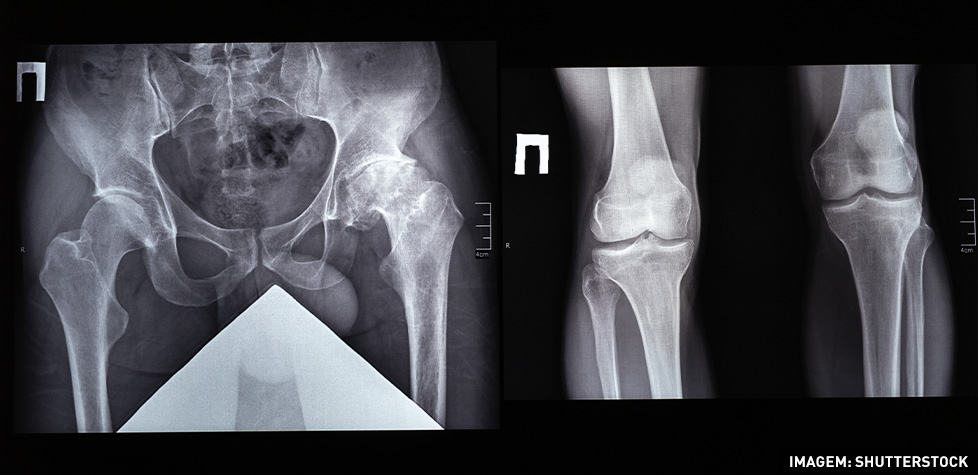

A coxartrose resulta de inflamação ou lesão da articulação coxo femoral com alterações da cartilagem, dor, inchaço e deformação da articulação. Pode ser definida por uma alteração da articulação coxo femoral (bacia e o fémur), com repercussões na mobilidade e presença de sintomatologia, dor. Na coxartrose existe o desgaste da cartilagem articular do acetábulo e da cabeça femoral.

A coxartrose ou artrose do quadril caracteriza e como osteoartrose de grande articulação; nas grandes articulações (quadril e joelho) costuma apresentar acometimento não inflamatório. Sinais semiológicos comuns: dor mecânica, rigidez, limitação de amplitude de movimento, crepitações e presença frequente de esporões ósseos (osteófitos).